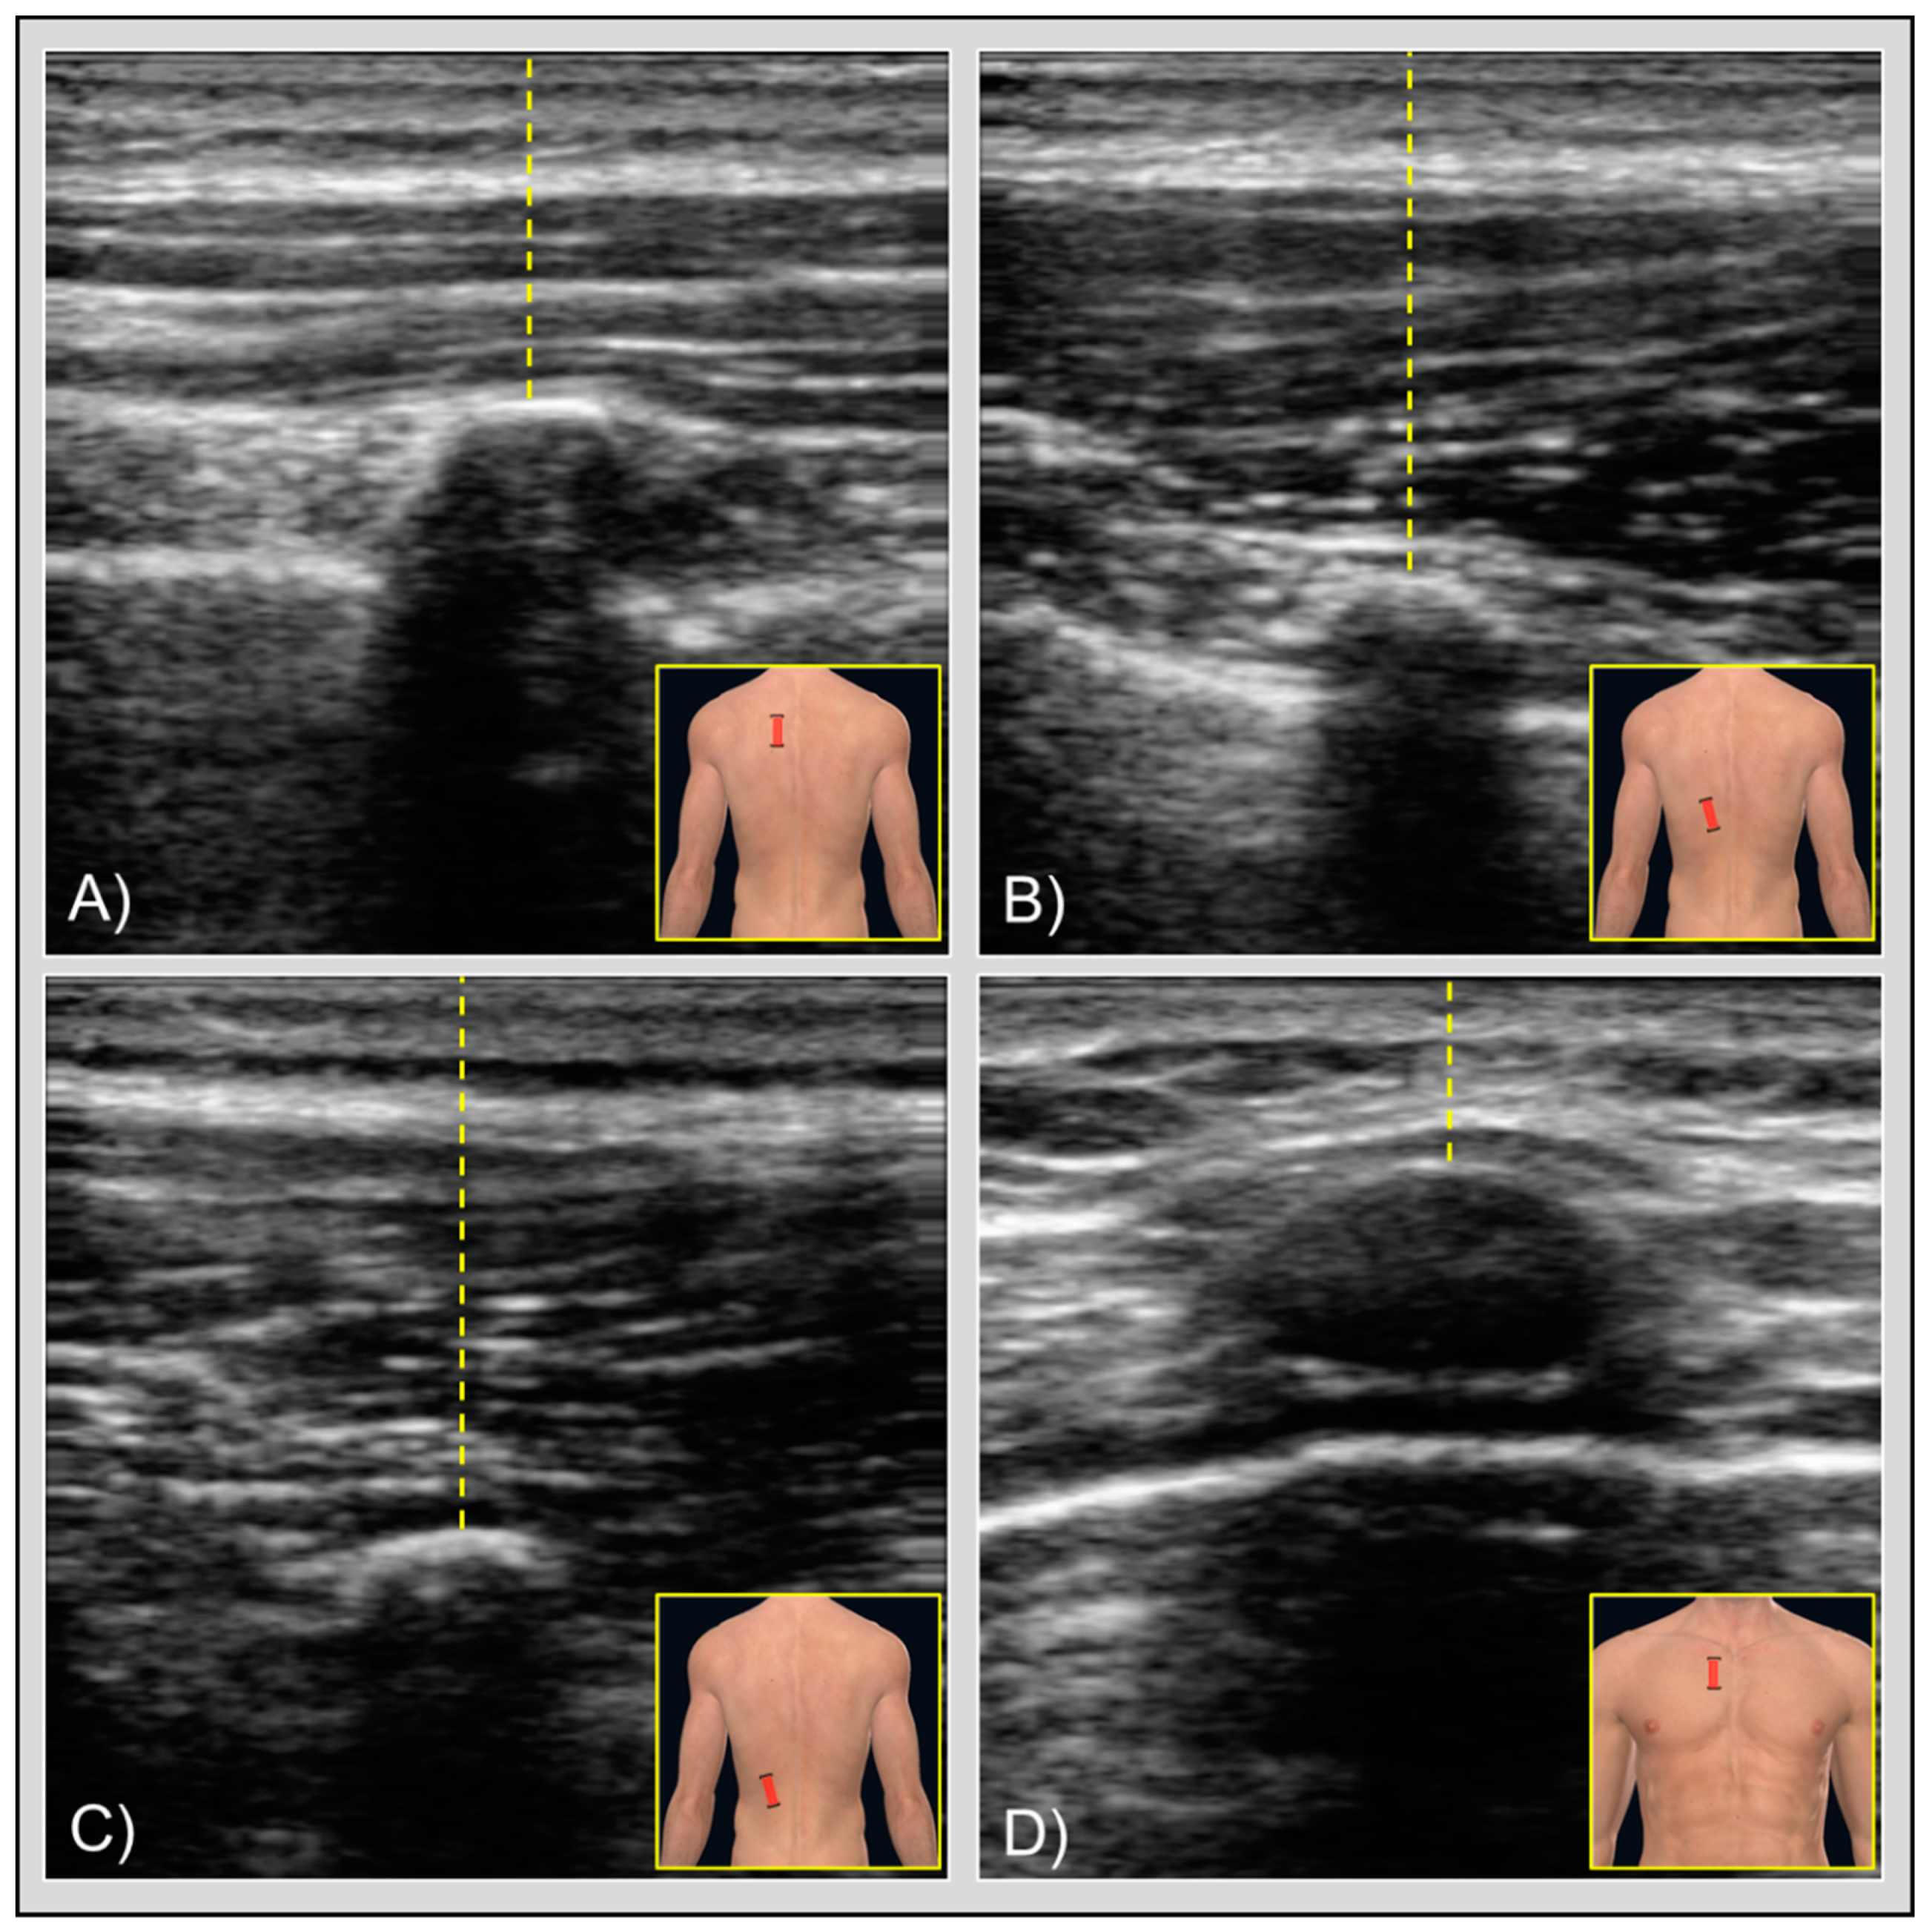

Figure 1. Figures showing the transducer placement (brackets) with ultrasound images and skin-to-rib measurement (yellow lines) for (A) rhomboid muscle, (B) lower trapezius muscle, (C) iliocostalis muscle, and (d) pectoralis major muscle. At the center of each image, the curved hyperechoic area represents the apex of the rib. Below the bone is visible the typical hypoechoic signal, also known as acoustic shadowing. Slightly deeper, in quadrants (A,B,D), you can also notice other hyperechoic tissues lateral to the bone, which represent the pleura. In the rhomboid muscle image (A), the different muscle layers are also visible: directly above the skin the middle trapezius muscle, just below it the rhomboid muscle, and around the rib the intercostal muscles. In the pectoralis major muscle image (D), the rib apex is less visible than in the other images due to the costal cartilages. - Lower trapezius (Figure 1B): 2–3 cm lateral to the spinous process of T8; transducer placed longitudinally.

- Iliocostalis (Figure 1C): 4–5 cm lateral to the spinous process of T10; transducer placed longitudinally.

- Pectoralis major (Figure 1D): lateral to the sternal origin and underneath the clavicular origin of the muscle; transducer placed transversally.